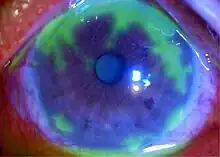

Disciform keratitis (Endothelial keratitis)

Endothelial keratitis manifests a central endothelitis in a disc-shaped manner. Longstanding corneal edema leads to permanent scarring and is the major cause of decreased vision associated with HSV.

Localized endothelitis (localized inflammation of corneal endothelial layer) is the cause of disciform keratitis.